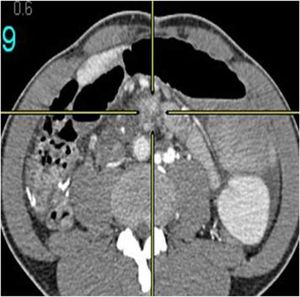

Mucinous cystadenom: 33-year-old female with abdominal distension and suspected ovarian mass. CT scan of abdomen and pelvis done with oral and intravenous contrast with multiple axial sections along with coronal and sagittal reformation.